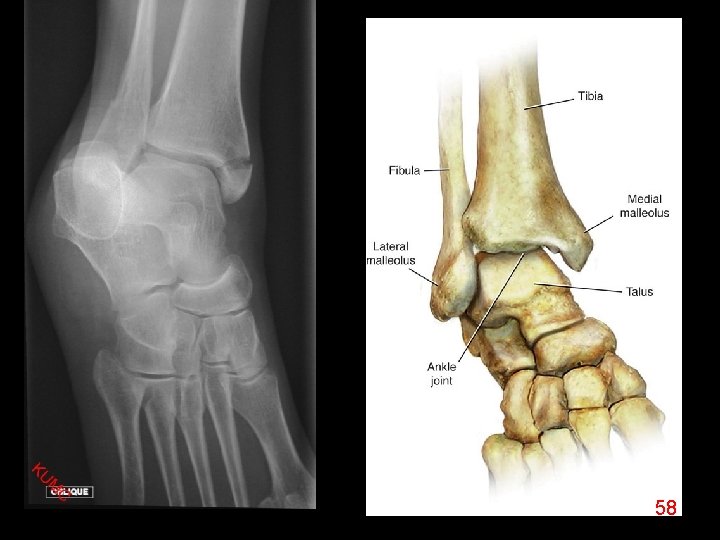

58